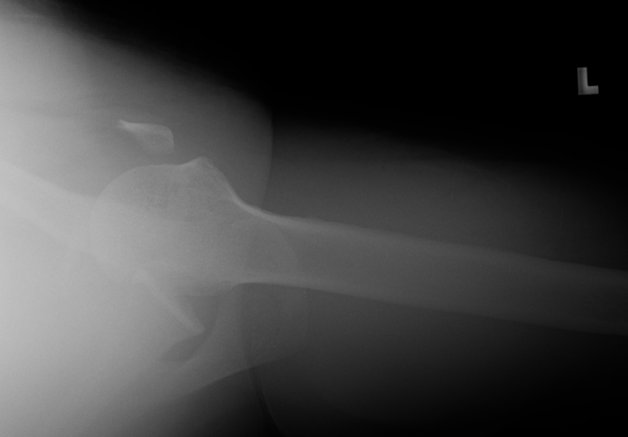

Return to Coracoid Fracture